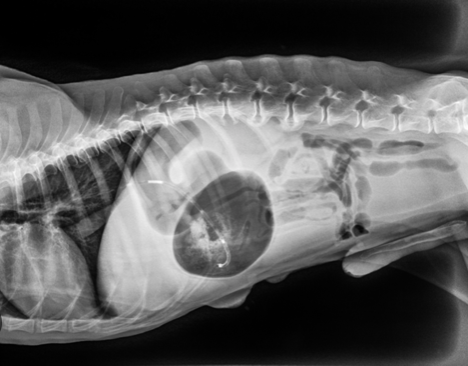

Bloat, also known as gastric dilatation and volvulus, or GDV, is not completely understood by veterinarians.

“GDV is a condition where the stomach twists and then fills with gas,” says Dr. Anna Stobnicki, DVM, a surgical intern at WestVet, an emergency animal hospital in Idaho. “Or the other way around—no one is sure whether it bloats then twists, or twists then bloats. Eventually, the dog’s stomach becomes distended with gas and puts pressure on the diaphragm, which can cause breathing problems. Additionally, the pressure cuts off the return blood flow to the heart, Stobnicki says. The extreme pressure within the stomach can cause tissue to die leading to stomach rupture, and sometimes the spleen twists with the stomach, which results in damage to splenic tissues as well.

After important steps like x-rays and bloodwork have been done and bloat has been diagnosed, surgery is the only treatment, Quammen says.

“The only way to treat it is to go into their abdomen surgically and untwist the stomach. The stomach is then sutured to the body wall to prevent it from twisting again. This is called a gastropexy,” Stobnicki says, noting that there can also be spleen issues that necessitate the spleen being taken out, as well as possibly part of the stomach being removed if the twisting is severe enough.